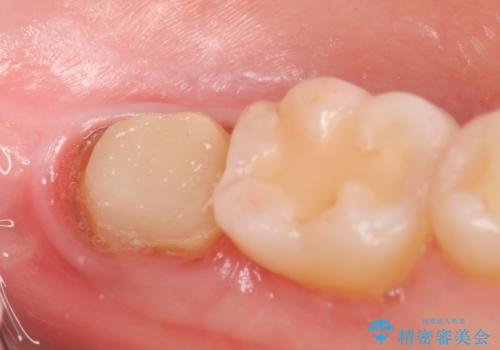

- 左下の一番奥の歯が時折激しく痛むので診て欲しいといらっしゃった方の症例です。以前に他院を受診したところ、そもそも被せ物を入れるスペースがないため抜歯しかないと言われたとのことでした。

診査の結果根尖病変を認めたため再根管治療を行った後に、被せ物を入れるスペースを作るため歯冠延長術を行いました。

歯冠延長術について

歯冠長延長術とは歯肉弁根尖側移動術とも言い、歯の高さが低くクラウン(被せ物)による治療が難しい場合に、歯茎を歯根方向に下げることで歯の高さを確保する手術です。歯の高さが十分にあることで、外れにくいしっかりとしたクラウンを被せることができます。